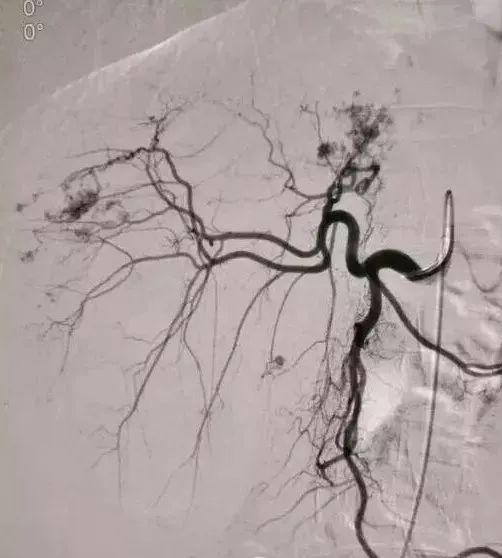

2、经导管血管栓塞法(Transcatheter embolization)

经原血管造影的导管或特制的导管,将栓塞物送至靶血管内,一是治疗内出血如外伤性脏器出血、溃疡病、肿瘤或原因未明的脏器出血。另一是用栓塞法治疗肿瘤,因肿瘤循环部分或全部被栓塞物阻断,以达控制肿瘤之生长,或作为手术切除的一种治疗手段;亦可用于非手术脏器切除,例如注射栓塞物质于脾动脉分支内,即部分性脾栓塞,以治疗脾功亢进,同时不影响脾脏的免疫功能。